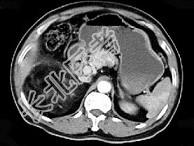

- 单项选择题男,59岁, 右侧腰背酸痛,CT检查如图所示, 应诊断为 ( )

A、右肾上腺腺瘤

B、右肾上腺转移瘤

C、右肾上腺髓样脂肪瘤

D、右腹膜后脂肪瘤

E、右肾血管平滑肌脂肪瘤